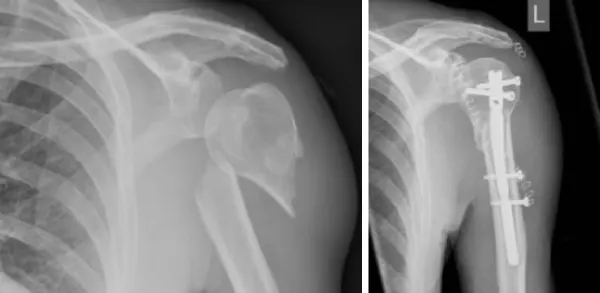

通过医学检查结果分析,此患者的诊断为肱骨近端骨折。这种骨折是指发生在肱骨(即上臂骨)上部接近肩关节处的骨折,是一种常见的上肢损伤类型,通常由外伤、跌倒或撞击等急性因素引起。根据临床影像学检查和医生的诊断,已确认为右侧的肱骨近端骨折。

肱骨近端骨折还分为简单骨折和复杂骨折两种,其中简单骨折多见于碎片较少的病例,而复杂骨折则涉及多处骨裂,可能需要植入钢板或钢钉来帮助协助愈合。这种区分对后期的治疗方法有较大影响。

而对于移位显著、复杂性多段骨折或涉及神经、血管损伤的病例,手术是不可避免的选择。骨折切开复位后,医生可能会通过钢板、钢钉或其他内固定装置来恢复骨骼的形态和功能。在个别严重骨折或出现明显关节炎的老年人中,可能会采取肩关节置换术作为较为终极的治疗方式。术后还需进行严格的康复锻炼,恢复肩部力量与活动范围。